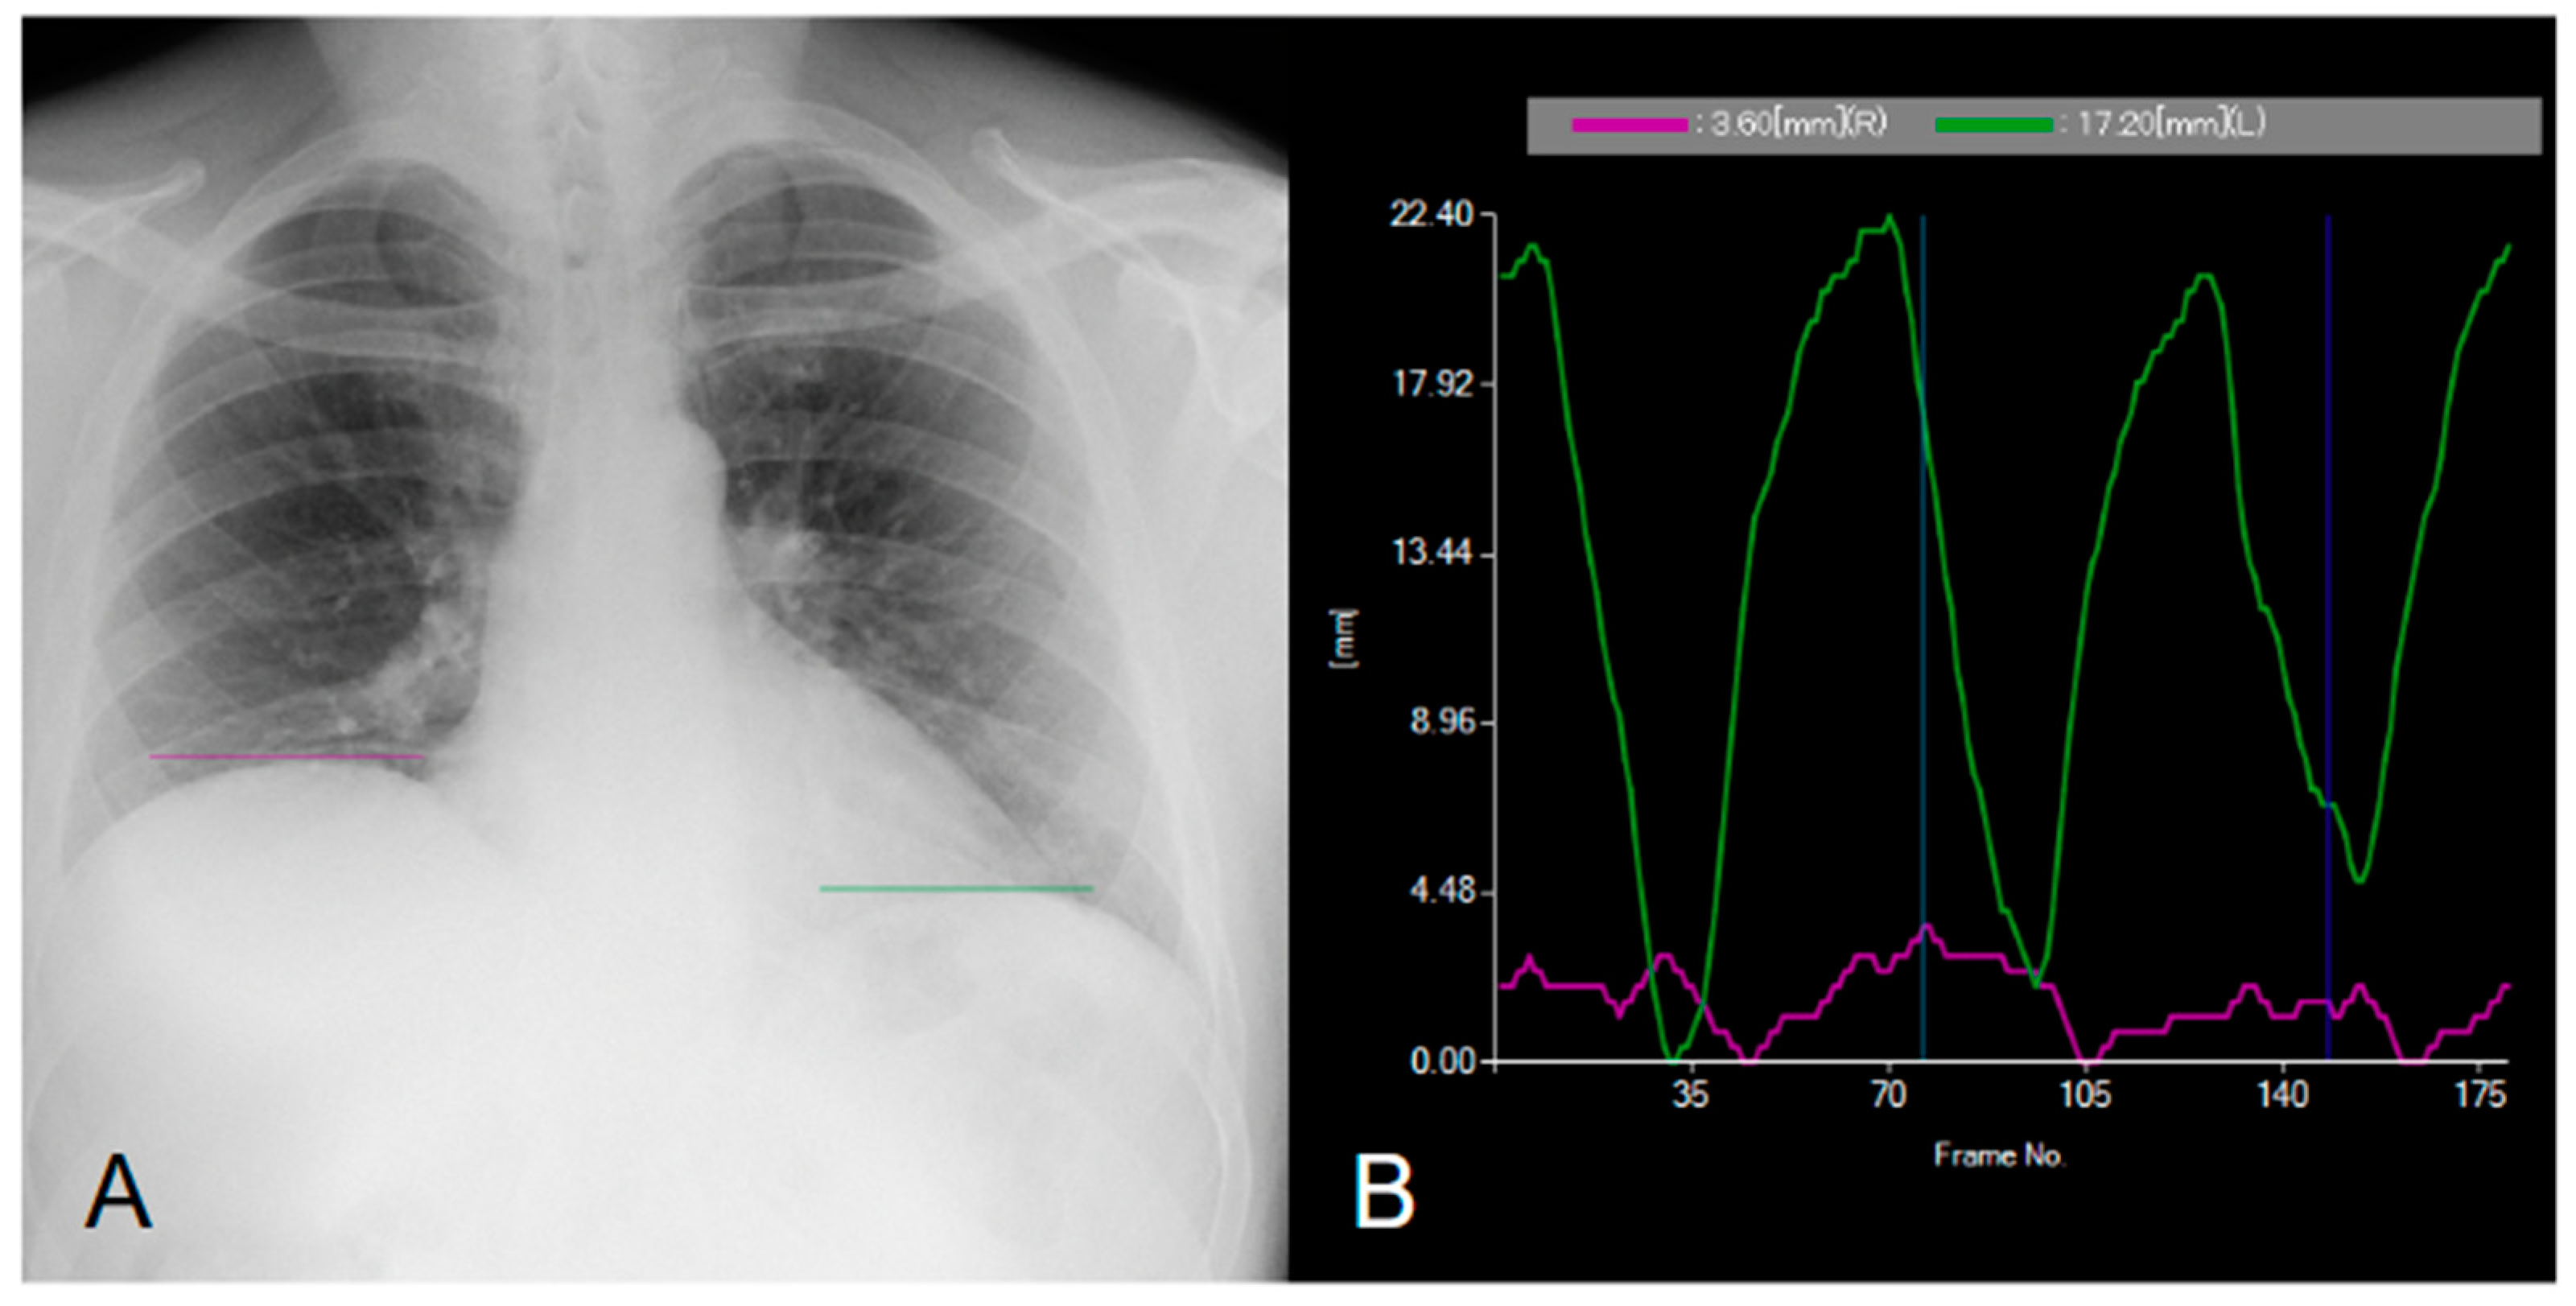

Figure 2.

Dynamic digital radiography confirming right hemidiaphragm paralysis. In (A), a dynamic acquisition of the chest in the posteroanterior projection is shown. In (B), the curves represent diaphragm dynamics: the system automatically tracks the highest point of each diaphragm dome and displays the movement using colored curves. The purple curve represents the right diaphragm, while the green curve represents the left diaphragm [1,2]. The movement of the right diaphragm is significantly reduced, indicating diaphragmatic dysfunction and confirming the clinical suspicion. In contrast, the movement of the left diaphragm is regular (Supplementary Material Video S1). The diagnosis of diaphragm dysfunction can be challenging [3]. Standard chest X-ray may suggest motion impairment or paralysis but fails to predict diaphragm function [3,4,5].